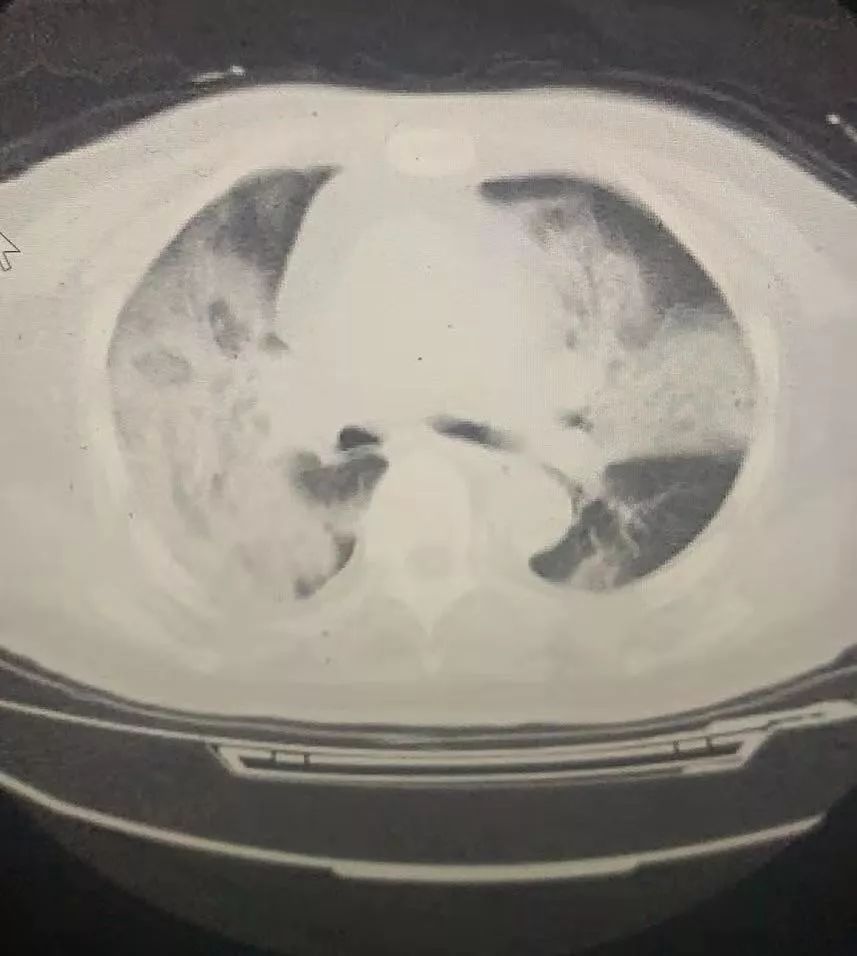

有一个医生和我说,她那天送到输液处的几乎全是“病毒肺”。CT片里,肺部像棉絮一样,最年轻的只有30岁。但我们实在没有能力收治。等他们打完针回家,又会造成更多感染。

一名疑似患者的肺部CT图,肺部基本全“白”了